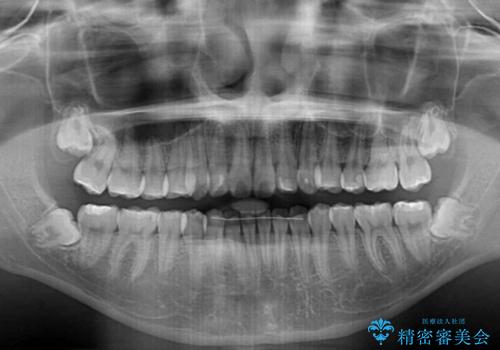

八重歯を効率よく改善するため、補助装置を使用して上顎の奥歯を後方に移動させました。

部活動をしながらでしたが、マウスピースをしっかりと装着してくださったので、1年半程度で終了することができました。